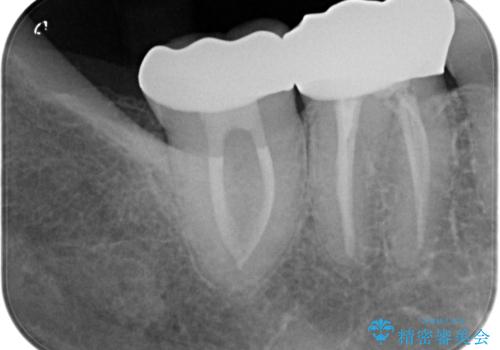

- 冷たいもので長引く痛みがあることを主訴に来院されました。

抜髄を行い、オールセラミッククラウンにて修復を行いました。

根管充填はバイオセラミックシーラーを使用しています。